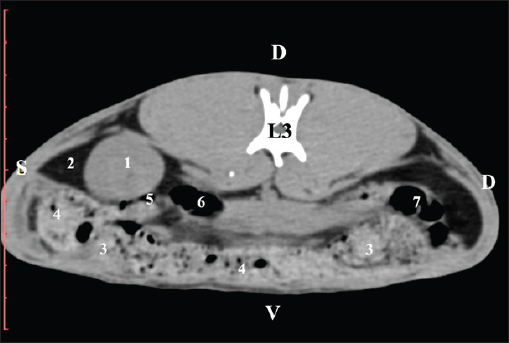

Fig. 7. Pre-contrast computed tomography (CT) anatomical scan of the regio-abdominis media at the caudal L3 edge level. (1) Ren dexter; (2) adipose collection; (3) cecum; (4) colon ascendens; (5) colon transversum; (6) colon descendens; (7) mesenterium. The transverse pre-contrast examination of the regio abdominis media at the L3 level (through the cranial part of the vertebra) revealed the left kidney’s extremitas cranialis as an oval soft tissue with normoattenuated soft tissue characteristics. Ventrally, the kidney was adjacent to the duodenal pars ascendens, ileum, colon ascendens, and colon descendens. Hypoattenuated abdominal adipose collections were observed around it (Figs. 8 and 9).

Fig. 8. Pre-contrast computed tomography (CT) anatomical scan of the regio-abdominis media at the cranial L3 edge level. (1) Ren sinister; (2) adipose collections; (3) cecum; (4) colon ascendens; (5) jejunum; (6) pars ascendens of the duodenum; (7) colon descendens; (8) colon transversum; (9) colon descendens.

Fig. 9. Pre-contrast computed tomography (CT) anatomical scan of the regio-abdominis media at the caudal L3 edge level. (1) Ren dexter; (2) adipose collections; (3) cecum; (4) colon ascendens; (5) jejunum; (6) pars ascendens of the duodenum; (7) colon descendens. The pre-contrast anatomical scan at the L4 level provided data about the location of the renal pelvis within the renal sinus. The initial part of the pelvis renalis appeared as a distinct funnel-shaped hypoattenuated soft tissue, whose central part was widened and formed the recessus renalis. The transition of the narrowed end of the renal pelvis into the hypoattenuated left ureter was without a sharp boundary. The left kidney was in contact with the cecum, colon ascendens, and colon transversum ventrally. Crista renalis was observed as a hypoattenuated linear soft tissue finding (Figs. 10 and 11).